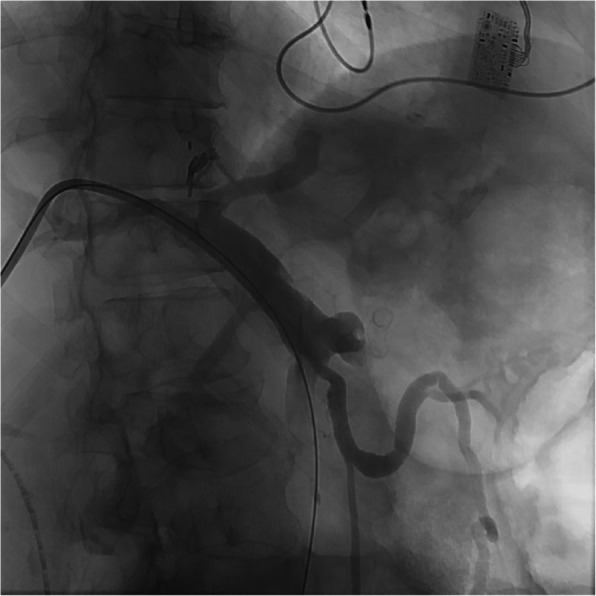

This case describes the endovascular treatment of a 55-year old female with a ruptured portal vein pseudoaneurysm secondary to a large stomach ulcer resulting in massive active hemorrhage into the adjacent stomach. This patient presented with persistent hypotension secondary to chronic GI blood loss and simultaneous septic shock. After an abrupt drop in blood pressure, the patient arrived in the angiography suite where the ruptured pseudoaneurysm was apparent on portal venogram. Emergent stent assisted coil embolization was performed to stabilize the patient and treat the portal vein pseudoaneurysm. To our knowledge, this case presents the only portal vein pseudoaneurysm secondary to a gastric ulcer.Level of Evidence Level 4, Case-report.

Abstract Image